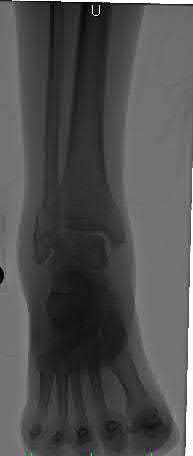

Figures A to C show radiographs of a 70 year-old male who fell on the ice 5 days ago. He could initially walk after the fall, but he is now unable to weight-bear on the leg due to pain. Physical examination shows diffuse ankle swelling, with no medial sided ankle tenderness. He is neurovascularly intact. The patient does not smoke and has no medical history. A gravity stress radiograph is demonstrated in Figure

D. After closed reduction, there is 2 mm of fracture displacement, no talar shift and the talocrural angle = 83 degrees. What is the most appropriate treatment?

Figure A demonstrates an AP radiograph of a Weber B fibula fracture with minimal medial clear space widening.